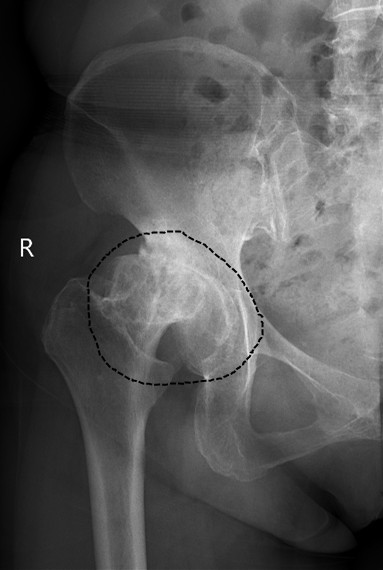

从图中所圈处对比不难发现,患者髋关节炎X线片显示:骨赘形成,髋臼缘增生,髋关节间隙变窄。关于髋关节炎,你了解多少?

(髋关节炎)